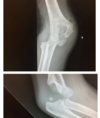

describe fracture

Extraarticular distal radius #

25% posterior displacement

45o dorsal angulation

Minimally displaced ulna styloid

How well did you know this?